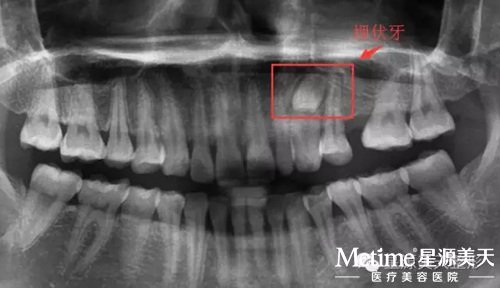

他被三博口腔的医护人员誉为全能的口腔医生,不管是拔复杂的埋伏牙/智齿、复杂的隐形矫治,还是修复类矫治,胡主任都会凭借专业的医学技能和丰富的临床经验,得以完美的解决。

每一次拔牙都需要拍片子 看牙齿的位置深度

横向生长的智齿 一般的牙医都不拔

埋伏牙、横向生长的智齿...,好多牙医都不敢拔的牙齿,对于胡主任来说,这都不算什么,20分钟就能搞定!